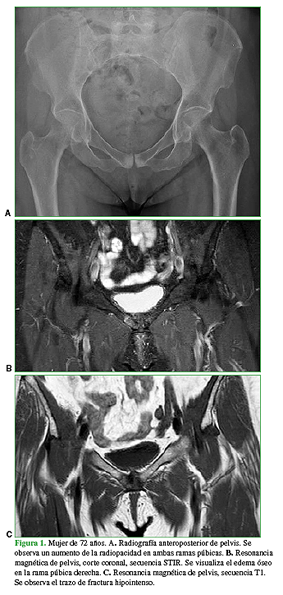

En el examen físico, se detecta dolor a la rotación interna y externa de la cadera derecha, dolor a la palpación del pubis derecho y dolor a la aducción contrarresistencia del miembro inferior derecho. Este cuadro inicialmente fue diagnosticado como una tendinitis insercional de los músculos aductores. Se solicitó una radiografía de pelvis (Figura 1A), en la que se observó un área radiopaca en la zona de la sínfisis púbica. Por el antecedente deportivo, la densidad mineral ósea baja y el tiempo de evolución del síntoma, se solicitó una resonancia magnética (Figura 1B y C) donde se confirmó una fractura por estrés del pubis derecho. El tratamiento inicial consistió en agentes analgésicos y antinflamatorios, sumados a reposo de actividades deportivas y rehabilitación física. Se derivó a la paciente al Servicio de Clínica Médica de nuestra institución para tener un asesoramiento del estado clínico y detectar algún factor de riesgo que pudiera influir en el tratamiento. Luego de seis meses de rehabilitación física, la paciente volvió a la consulta con limitación al caminar y un dolor de las mismas características, por lo que se decidió repetir los estudios por imágenes. Nuevamente, se observó el aumento de la radiopacidad en las radiografías simples y un idéntico foco de intensidad aumentada con edema óseo en el pubis derecho, en la resonancia magnética (Figura 2).